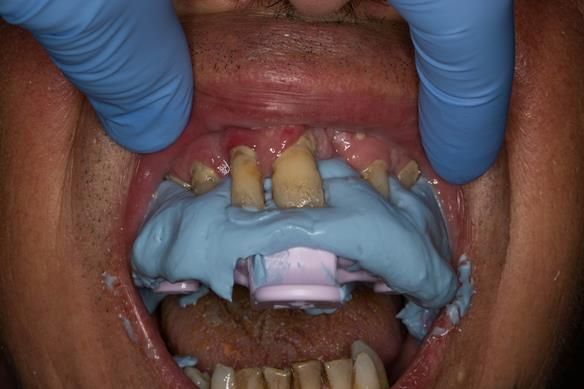

This newsletter describes in step by step detail the transition from acrylic based immediate dentures to metal based definitive dentures.

- Extraction of all upper teeth and LR5 and LL4 and fitting of immediate acrylic based (Mk 1) dentures - complete upper and lower partial

- Reviews of the immediate dentures and relines as needed over 9 - 12 months

- Definitive dentures (Mk 2) – complete upper metal reinforced and lower cobalt chromium based partial of hygienic Scandinavian design to be made 9 - 12 months after extractions of all upper teeth and LR5 and LL4

The clinical situation and treatment process is shown in detail below with photographs.